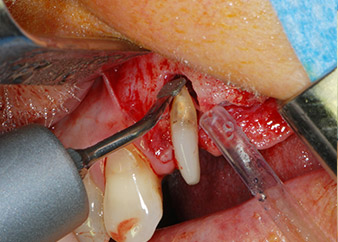

Nous avons toutefois maintenu notre projet initial de conservation des deux dents comme piliers temporaires d'un bridge pendant la période de six mois nécessaire à l'ostéointégration des implants. À la prochaine incision, la situation devrait être réétudiée. Premièrement, afin de gérer le problème endoparodontal, la surface de racine restante a été soigneusement débridée à l'aide d'un équipement piézoélectrique (Piezomed, W&H, utilisé avec l'insert en forme de spatule S1, initialement conçu pour limer la paroi sinusienne latérale) (Fig. 4).

Puis l'apex a été limé à l'aide du même instrument afin d'éliminer les tissus apicaux infectés résiduels et de réduire les éventuelles ramifications des canaux radiculaires (apicectomie) (Fig. 5). Il n'a pas été nécessaire de procéder à une obturation rétrograde car l'obturation orthograde venait juste d'être reprise.